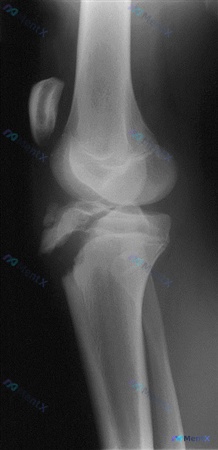

【病例资料】15 岁男性,跳台滑雪着陆后右膝急性疼痛肿胀。X 光示胫骨近端前侧骨折伴骨块分离,软组织明显肿胀。高能量创伤机制下,哪种伴随情况需优先警惕?

📋答案:急性骨筋膜室综合征(ACS)